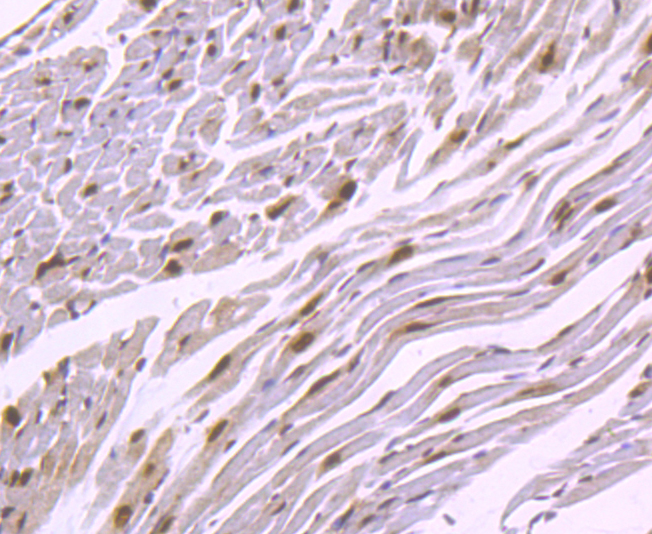

IHC: 1:100-1:500

文献和实验:使用 Anti-phospho-Akt (Ser473) Rabbit mAb 对石蜡包埋的人乳腺癌组织进行免疫组织化学分析。(图 A)使用免疫组化试剂盒M&R HRP/DAB Detection IHC Kit,抗体 1:100 稀释;(图 B) 采用普通免疫组化试剂盒,抗体 1:25 稀释。 图 6 免疫组化实验检测 Erk1/2 表达 注:使用 Anti-Erk1/2 Mouse mAb与p44/42 MAPK (Erk1/2)Rabbit mAb 对正常小鼠心脏组织进行免疫